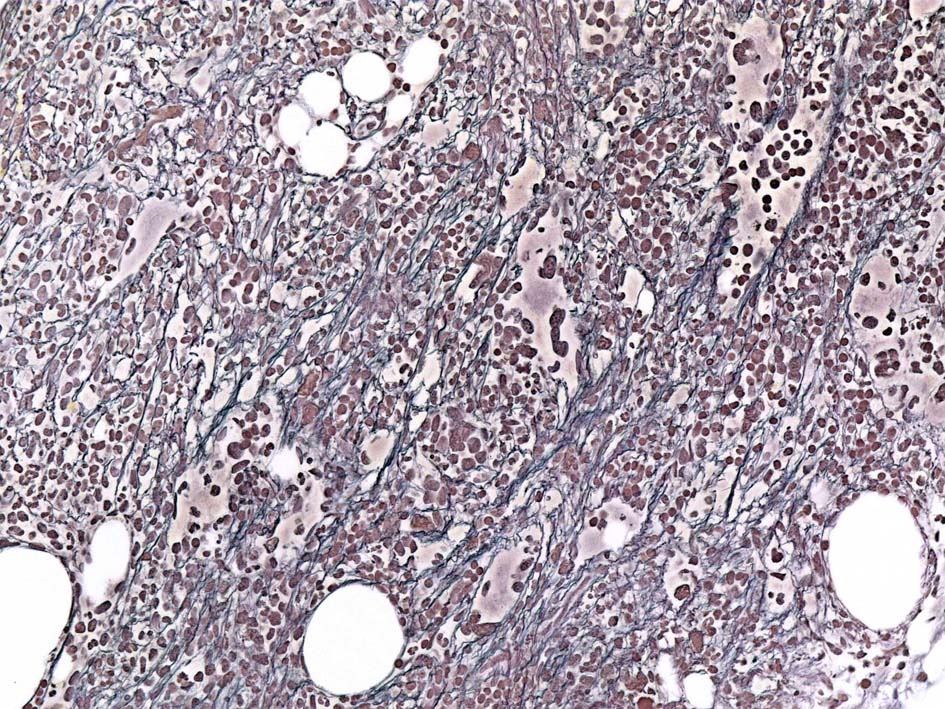

Case01; Meylofibrosis, overt fibrosis

77year-old female. 40歳時polycythemia veraと診断されていた.

[注] この症例は詳細は不明であるが, 過去にPVと診断されているため, PVに伴う二次性のmyelofibrosisの診断になる.

黒染する弾性線維の増生のほか, 赤く染まる膠原線維の増生が確認される. MF-2 fibrosis. 鍍銀染色の核染色をすると膠原線維の赤染がわからなくなるので行わない.